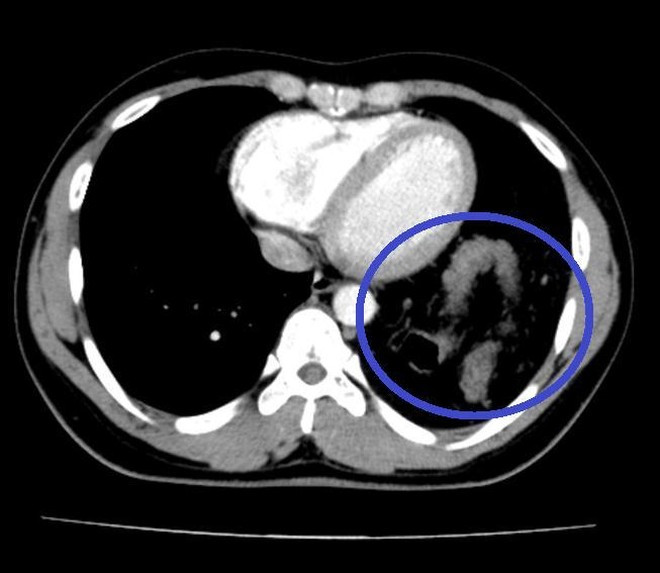

Tưởng hậu COVID-19, bệnh nhân đi khám phát hiện bị vỡ cơ hoành ảnh 1Đại tràng nằm trong ngực trái trên hình ảnh Cắt lớp vi tính ngực. (Nguồn: anninhthudo)

Bệnh nhân được hoàn thiện thêm các xét nghiệm cận lâm sàng và hội chẩn thêm các chuyên khoa, chụp cắt lớp khẳng định có thoát vị tạng bụng qua cơ hoành lên ngực trái.

Khi đưa máy soi vào ổ bụng, phẫu thuật viên nhận thấy gần toàn bộ đại tràng ngang, lách, dạ dày và mạc nối lớn đã chui qua cơ hoành lên khoang màng phổi bên trái. Sau khi đưa các tạng trên trở lại ổ bụng, tổn thương cơ hoành bên trái lộ rõ là một lỗ khuyết rộng khoảng 6x8cm.

Đây chính là nguyên nhân gây ra thoát vị, kết hợp với tiền sử có chấn thương, chẩn đoán trong mổ là thoát vị hoành trái do vỡ cơ hoành.